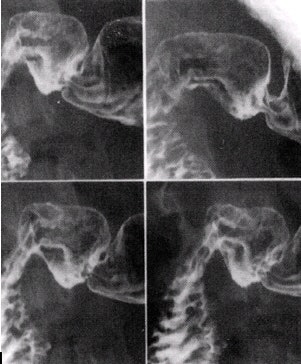

![]() |

| Images of the duodenal bulb in four slightly different views (10 x 12 image receptor, 4 on 1). Image courtesy of Dr. Naveed Ahmad. |

- With the tabletop horizontal and patient in right lateral position, image the duodenal bulb. Visualize the barium-filled duodenal bulb and obtain at least four slightly different views. If the bulb is not well seen, have the patient inhale deeply and stop breathing briefly to improve visualization of the bulb. Alternatively, the patient can be placed prone and the duodenal bulb can be compressed from underneath by using a balloon compression paddle.